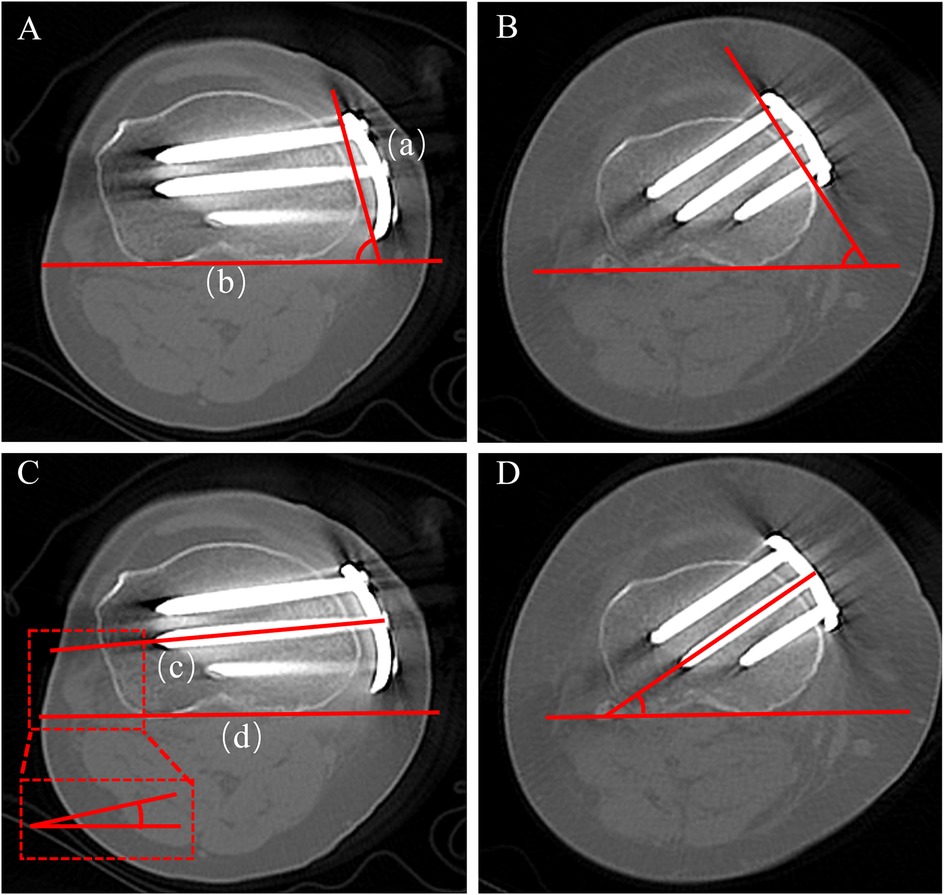

Background: High tibial osteotomy (HTO) corrects varus malalignment and unloads the medial knee compartment, yet the conventional T-shaped locking plate may cause discomfort due to suboptimal anatomic conformity. We developed a novel locking plate to improve anatomic fit and fixation stability and compared it with the T-shaped plate in Anterior Popliteus Transtibial-tuberosity high tibial osteotomy (APTT-HTO). Methods: This single-center retrospective observational comparative study included 14 consecutive patients who underwent APTT-HTO between August 2024 and June 2025. Patients were grouped by implant type (novel plate: n = 7; T-shaped plate: n = 7). Postoperative CT quantified plate orientation/position, plate–bone conformity (gap and position mismatch), screw alignment, and standard alignment parameters (hip–knee– ankle angle [HKA], posterior tibial slope [PTS]). Results: The novel plate showed more posteromedial placement and superior anatomic conformity. The plate angle relative to the posterior tibial condylar reference line was larger with the novel plate (74.49° ± 8.76°) than with the T-shaped plate (62.62° ± 7.05°, P<0.05). The proximal central screw–plate angle was smaller (5.70° ± 4.80° vs 27.48° ± 6.05°, P<0.05), the plate–bone gap was reduced (1.84 ± 0.68 mm vs 2.98 ± 0.38 mm, P<0.05), and plate position mismatch was lower (20.20% ± 7.70% vs 37.70% ± 10.00%, P<0.05). Proximal and distal offsets considered separately were not significantly different (P>0.05). Both groups achieved the planned coronal correction, and sagittal PTS remained stable (P>0.05). Conclusions: In this CT-based cohort, the novel anatomically contoured locking plate achieved superior anatomic conformity in APTT-HTO—characterized by more posteromedial positioning, a more favorable screw trajectory, and improved plate–bone apposition—compared with a conventional T-shaped plate. These findings warrant confirmation in larger, prospective studies.